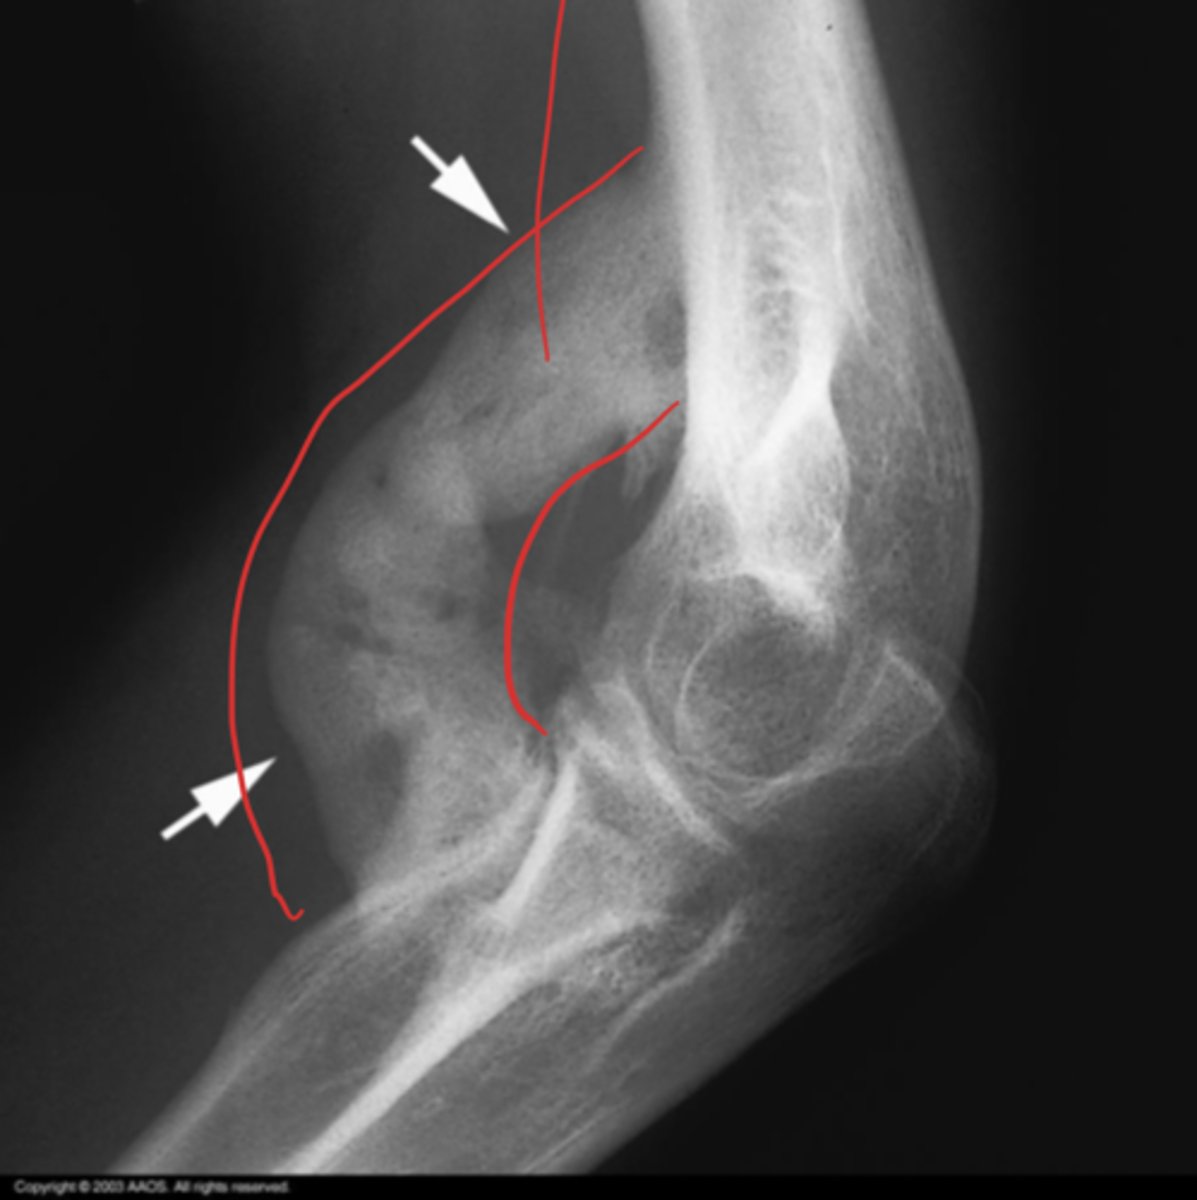

abnormal supinator sign

What is the issue?

positive fat pad sign